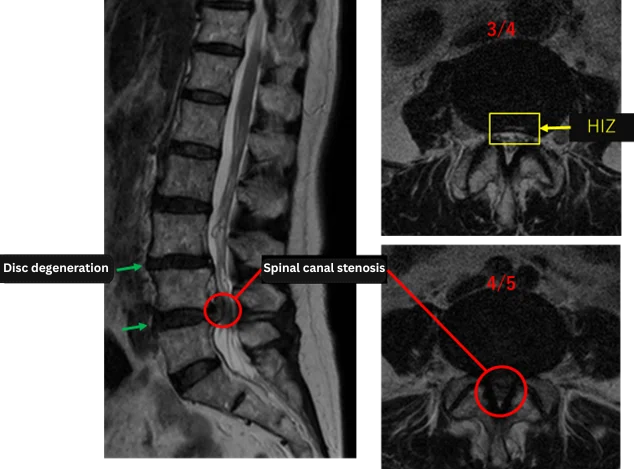

Imaging and findings

L1/2: Normal

L2/3: Normal

L3/4: Disc degeneration, bulging, high-intensity zone (HIZ)

L4/5: Disc degeneration, bulging, bilateral foraminal stenosis, spinal canal stenosis

L5/S: Normal

The above findings were also observed on the imaging.

These findings suggest that disc degeneration, foraminal stenosis, and spinal canal stenosis at L3/4 and L4/5 are likely the main causes of her symptoms.